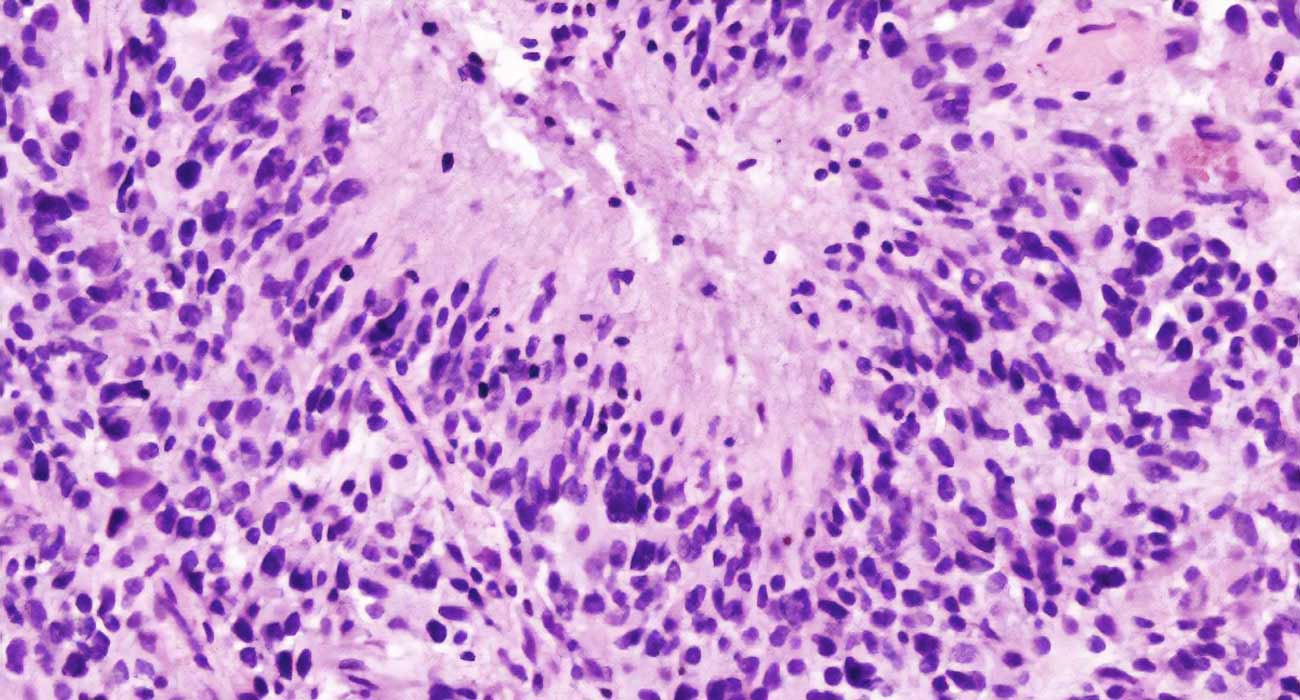

Este grupo estudia la biología de los tumores cerebrales, un tipo de cáncer con supervivencia muy limitada. Se busca identificar mecanismos clave que regulen el desarrollo tumoral y la respuesta inmune, con el objetivo de desarrollar terapias innovadoras que mejoren la calidad y la esperanza de vida de los pacientes.